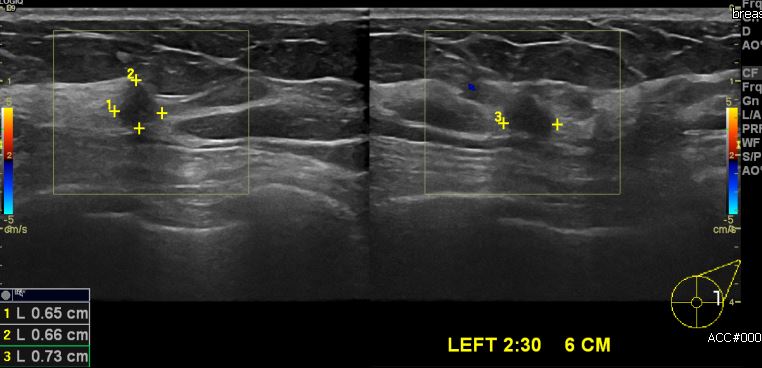

건강검진상 이상 소견으로 내원하신 50대 여성분으로  본원 유방 초음파 시행후 좌측 유방의 2시30분 방향에 6cm 떨어진 거리의 혹 중심핵생검 시행하여 좌측 침윤성 유관암

진단 되었습니다.